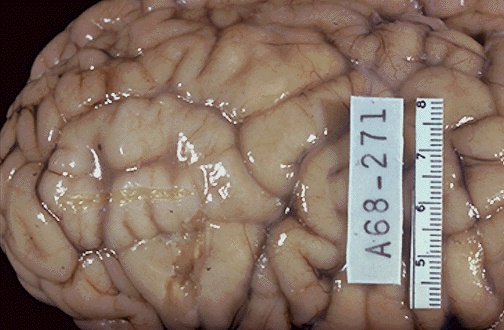

This area of firm whitened gyri that are broader than the surrounding normal gyri is typical for tuberous sclerosis. [Image contributed by Jeannette J. Townsend, MD, University of Utah]